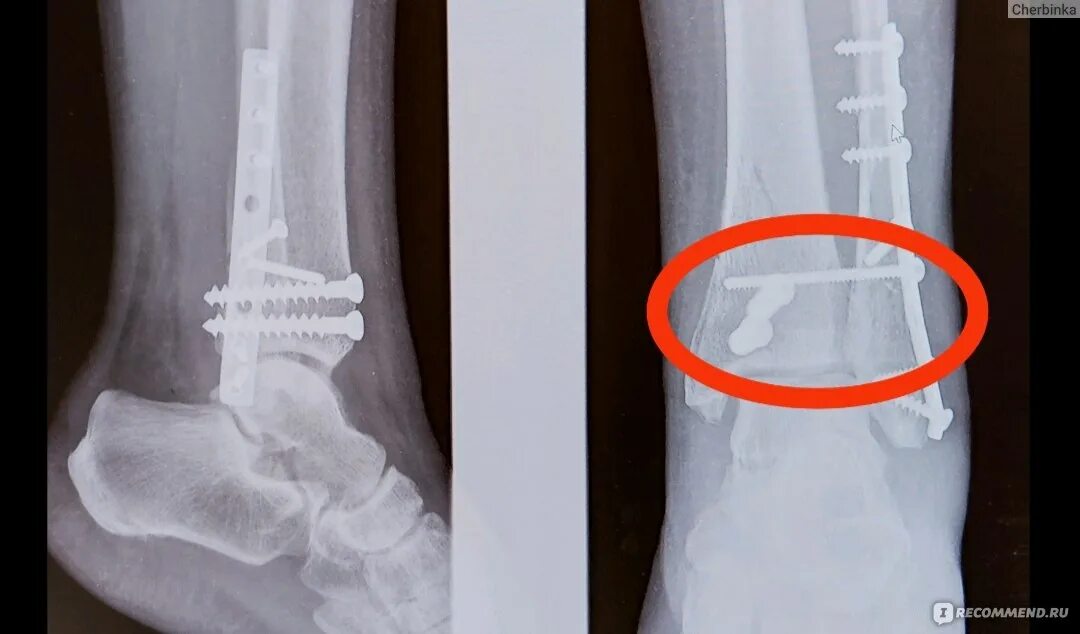

Сколько срастается стопа